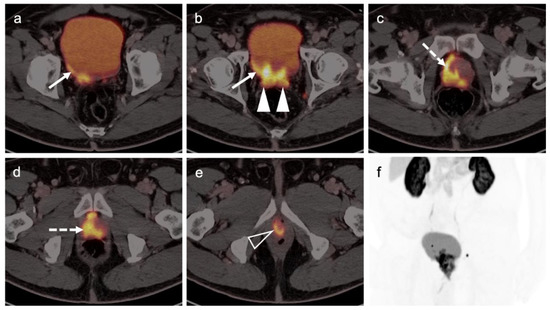

3.1. Prostate Cancer

3.2. Urothelial Carcinoma